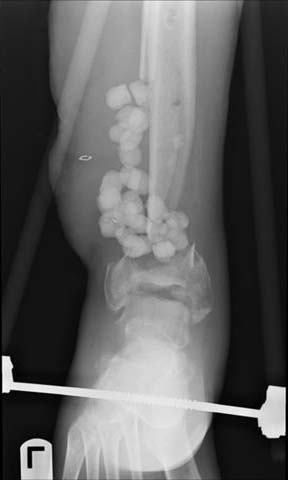

30 year old male, 10 weeks out from open fracture of distal tibia. Large anterolateral flap which looks healthy and just needs some STSG. Now shows up in my clinic. Slightly decreased sensation in dorsal foot, plantar normal. Decreased toe extension presumably from loss of anterior compartment and muscle damage.

My vote is acute shortening, tibio-talar fusion, re-lengthening through a proximal corticotomy (bifocal compression-distraction).

Acute shortening to till you get bone contact between the proximal and distal fragments.

Minimal internal fixation oriented tranversely, subchondral, to secure the medial malleolus

Fill in the remaining area with cancellous bone graft Lengthen thru a proximal corticotomy

Sacrificing the distal fragment entirely, and aiming for a tibio talar fusion is another option....

I favor shortening, and trying to preserve the ankle segment with some internal fixation- plate vs crossed screws. Bone graft well. Ankle motion is sometimes suprising because of the shortening. Let this heal, then lengthen above using your method of choice. I prefer monorail technique.